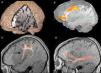

La afasia es una alteración adquirida del lenguaje debida a una lesión cerebral, que se caracteriza por errores en la producción, la denominación o la comprensión del lenguaje. Aunque la mayoría de las afasias suelen ser mixtas, desde un punto de vista práctico se clasifican en diferentes tipos según sus rasgos clínicos principales: afasia de Broca, afasia de Wernicke, afasia de conducción, afasia transcortical y alexia con o sin agrafia. Presentamos los hallazgos clínicos de los principales subtipos representándolos con casos radiológicos, y proporcionamos una revisión actualizada de la red del lenguaje con imágenes de resonancia funcional y de tractografía.

Aphasia is an acquired language disorder due to a cerebral lesion; it is characterized by errors in production, denomination, or comprehension of language. Although most aphasias are mixed, from a practical point of view they are classified into different types according to their main clinical features: Broca's aphasia, Wernicke's aphasia, conduction aphasia, transcortical aphasia, and alexia with or without agraphia. We present the clinical findings for the main subtypes of aphasia, illustrating them with imaging cases, and we provide an up-to-date review of the language network with images from functional magnetic resonance imaging and tractography.